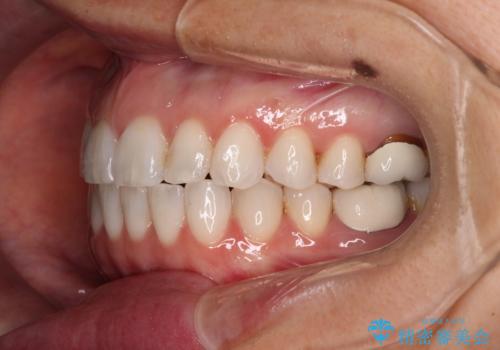

- 前歯のデコボコと上下スペースと前歯の隙間を気にして来院された患者様です。

目立たない装置を希望とのことでインビザラインにより、デコボコを解消しつつ、上下の前歯の隙間を閉じていくこととしました。

デコボコはあっという間に解消されましたが、上下前歯の隙間がなかなか解消されませんでした。

飲み込みの際に舌を前方に突出する癖があり、飲み込みの度に前歯に強く接触していたため、上下前歯の隙間が維持されていました。

舌の訓練を徹底していただいたことで、徐々に隙間は解消され、きれいな歯列に整えることができました。